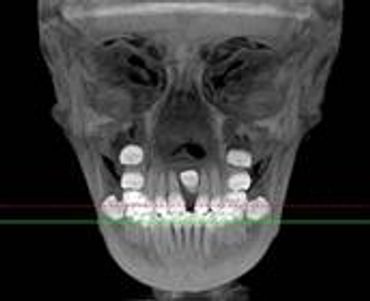

What is CBCT- Cone Beam Computer Tomography?

CBCT is a digital x-ray scanner specifically designed for scanning the head and jaws. The scanner rotates 360 degrees around the patient's head in a matter of seconds. The x-ray is a low energy fixed anode tube similarly used in panoramic machines. This method reduces radiation scatter common to most conventional x-rays. The cone shaped x-ray provides 360 views that can be presented in 2D image and 3D volume for advanced planning and diagnostic support.

[Why the need for a CBCT?]

This one scan provides more images than plain film conventional imaging, with complete visualization of the patient's entire maxillofacial region. These images clearly display TM disorders, impacted teeth, critical bone and tooth relationships, oral- nasal airways, para-nasal sinus, mandibular canal and difficult to see pathologies within one volume. The user friendly software system reconstructs true size, distortion free, high resolution images.

[Why is this better for patients?]

The CBCT scanner is fast, comfortable (nothing goes in the mouth), and painless for patients. It provides a complete set of maxillofacial images with less radiation than conventional orthodontic and medical type CT work-ups. CBCT now can re-create true size cephalometric and panoramic images, virtually eliminating the need for conventional orthodontic x-rays, so your patients will be comforted by the knowledge that you have all the information needed to evaluate and plan their treatment